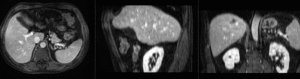

comparing kidney alignment at different registration stages